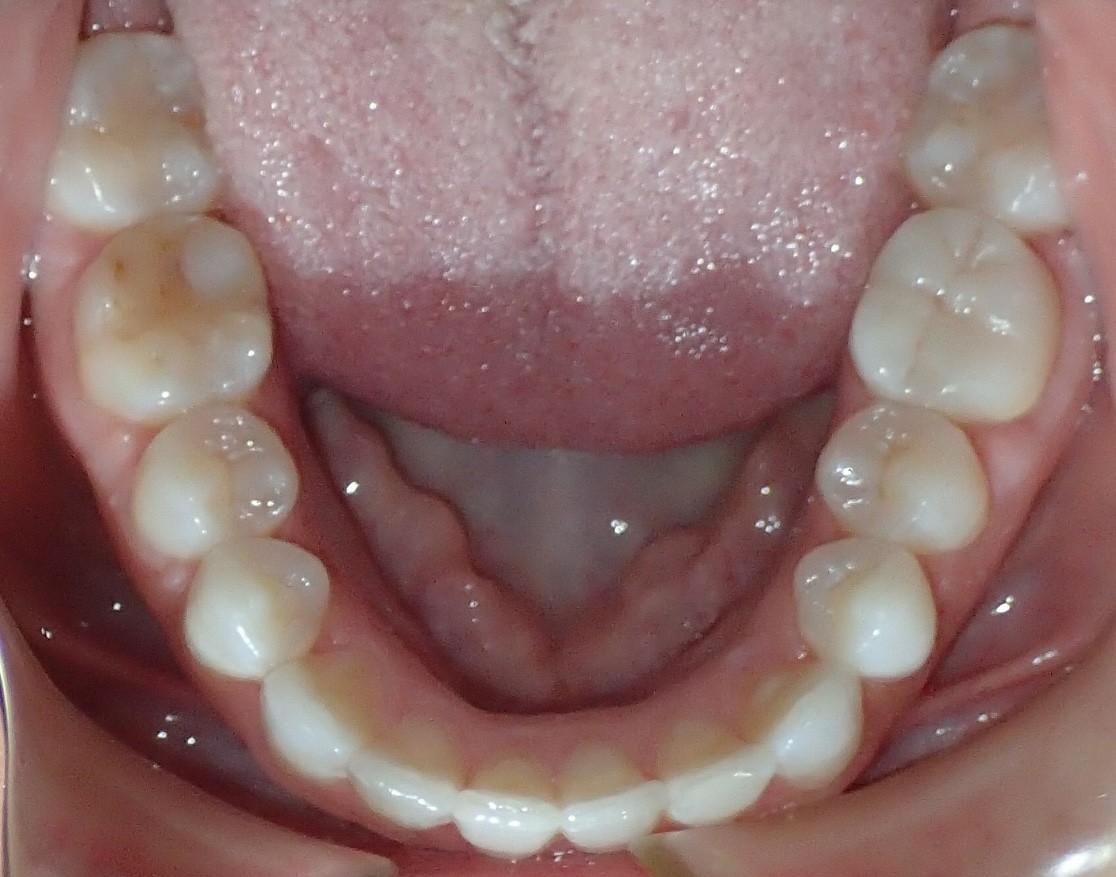

Initial treatment

INTRAORAL